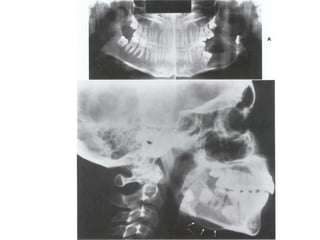

Sarcoma

This tumor, which affects males twice as

females, exhibit a predilection for the

mandible.

Radiographically, bone destruction as well as

new bone formation and osteolysis can be

observed, along with perforation of the

compact bone with spicules (sunrays

effect), where the lesion borders on the

soft tissues

Mixed form of ostiosarcoma: In addition to areas of

new bone formation, osteolysis and

destruction of the compact bone can be

observed. Note the areas of spicules

(arrows)